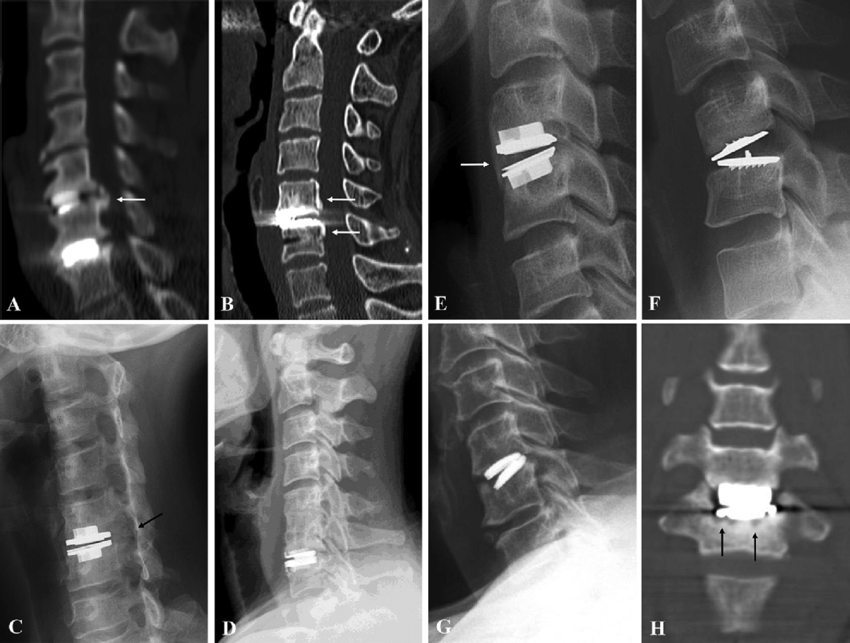

- Tạo đặc điểm bề mặt phù hợp: Các phương pháp thực hiện bao gồm tạo các rãnh (keels), gai (spikes), lưới dây (wire mesh), hoặc các lỗ nhỏ (pores).

- Cố định bằng vít: Một số loại đĩa đệm nhân tạo được cố định vào các đốt sống bằng vít.

Tuy nhiên, các rủi ro chung vẫn có thể xảy ra, bao gồm cố định không đủ chắc chắn, xương phát triển quá mức trên đĩa đệm hoặc gãy vít.

- Sự cố định với xương: Nếu sự gắn kết giữa đĩa đệm và xương không hoàn toàn hoặc không đủ chắc chắn, độ ổn định của đĩa đệm sẽ bị giảm.

- Sụt lún: Sụt lún có thể gây ra truyền tải lực bất thường trên cột sống và dẫn đến đau cổ. Có thể tránh được tình trạng này bằng cách chuẩn bị các mâm đĩa đệm nhân tạo một cách thích hợp để khớp với góc chính xác trong khoang đĩa đệm.